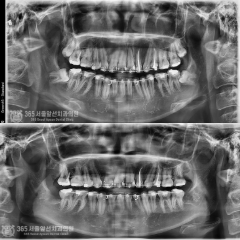

전체임플란트, 발치와 동시에 전체 임플란트 치료를 시행한 환자분

안녕하세요. 주안역치과 365서울앞선치과의원입니다.오늘은 발치와 동시에 전체 임플란트 수술을 한 원데이..